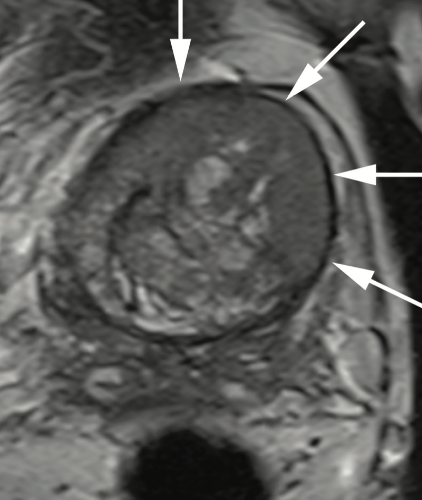

![A statistically significant benefit in terms of radiographic progression-free survival (rPFS) was noted with the use of olaparib (Lynparza) vs placebo in combination with abiraterone acetate (Zytiga) for patients with frontline metastatic castration-resistant prostate cancer (mCRPC), according to results of the phase 3 PROpel trial (NCT03732820) that were presented at the 2022 Genitourinary Cancers Symposium.1 The median investigator-assessed rPFS was 24.8 months with olaparib/abiraterone vs 16.6 months with placebo/abiraterone (HR, 0.66; 95% CI, 0.54-0.81; P <.0001), which translated to a 34% reduction in the risk of radiographic disease progression or death. The 1- and 2-year rPFS rates were 71.8% and 51.4% in the olaparib/abiraterone arm, respectively; these rates were 63.4% and 33.6% with placebo/abiraterone, respectively. When evaluated by blinded independent central review, the median rPFS with olaparib/abiraterone was 27.6 months vs 16.4 months with placebo/abiraterone, leading to a 39% reduction in the risk of radiographic disease progression or death (HR, 0.61; 95% CI, 0.49-0.74; P <.0001). The 1- and 2-year rPFS rates with olaparib plus abiraterone were 73.8% and 53.7%, respectively. In the placebo/abiraterone arm, these rates were 60.6% and 34.1%, respectively. Lead study author Fred Saad, MD, FRCS, said that PROpel is the first combination approach to deliver consistent clinical benefits for patients in the first-line mCRPC setting, irrespective of homologous recombination repair (HRR) mutation status. “This benefit led to what I think is the longest rPFS we have seen to date in metastatic CRPC beyond 2 years,” Saad, who is professor and chairman of urology and director of Genitourinary Oncology at the University of Montreal Hospital Center, as well as the Raymond Garneau Chair in Prostate Cancer Research and director of Clinical Research and the Molecular Oncology Research Laboratory in Prostate Cancer, said in a presentation during the meeting. Patients with mCRPC who are treated in the frontline setting have a median survival of approximately 3 years in clinical trial settings, Saad noted, adding that about half of patients in real-world practice only receive 1 line of active treatment. Here, the median survival is less than 2 years, underscoring an unmet need to improve outcomes in the up-front setting. Previously, data with olaparib in mCRPC have shown encouraging results. The phase 3 PROfound trial (NCT02987543) demonstrated significantly prolonged rPFS and overall survival (OS) in patients with mCRPC following a next-generation hormonal agent (NHA) with HRR gene alterations.2 Additionally, a phase 2 trial (NCT01972217) of olaparib and abiraterone showed prolonged investigator-assessed rPFS vs placebo/abiraterone in patients with mCRPC following treatment with docetaxel, regardless of HRR status (HR, 0.65; 95% CI, 0.44-0.97; P = .034).3 In the international, double-blind, phase 3 PROpel trial, investigators randomized patients with mCRPC in the first-line setting 1:1 to receive olaparib at 300 mg twice daily plus abiraterone at 1000 mg daily (n = 399) or placebo and abiraterone at 1000 mg daily (n = 397). Patients could have received docetaxel in the metastatic hormone-sensitive prostate cancer (mHSPC) setting, but no prior abiraterone was allowed. Other NHAs were permitted if they were stopped at least 12 months prior to study enrollment. Patients also had ongoing androgen deprivation therapy and an ECOG performance status of 0 or 1. Stratification factors included site of distant metastases (bone-only vs visceral vs other) and prior taxane in the mHSPC setting (yes vs no). The primary end point was investigator-assessed rPFS, with OS as a secondary end point. Additional outcome measures included time to first subsequent therapy or death (TFST), time to second progression or death (PFS2), objective response rate (ORR), HRR mutation prevalence (retrospective testing), health-related quality of life, and safety and tolerability. Baseline characteristics were well-balanced between the 2 arms. The median age was 69.5 years (range, 43-91), and most patients had an ECOG performance status of 0 (70.1%). Of note, symptomatic patients (Brief Pain Inventory-Short Form ≥4 and/or opiate use) comprised 25.8% and 20.2% of olaparib- and placebo-treated patients, respectively; 22.5% of patients had received docetaxel at the mHSPC stage. Additionally, patients either had HRR mutations (27.8% with olaparib vs 29.0% with placebo), non-HRR mutations (69.9% vs 68.8%, respectively), or unknown HRR mutation status (2.3% each). The median PSA was 17.90 ug/L (interquartile range [IQR], 6.09-67.00) with olaparib/abiraterone and 16.81 ug/L (IQR, 6.26-53.30) with placebo/abiraterone. Most metastases occurred in the bone at 87.5% and 85.4% of patients, respectively. Additional findings showed that the rPFS benefit was observed across all prespecified subgroups, including age (<65 years, HR, 0.51; 95% CI, 0.35-0.75; ≥65 years, HR, 0.78; 95% CI, 0.62-0.98), site of distant metastases (bone-only, HR, 0.73; 95% CI, 0.54-0.98; visceral, HR, 0.62; 95% CI, 0.39-0.99; other, HR, 0.62; 95% CI, 0.44-0.85) prior docetaxel (yes, HR, 0.61; 95% CI, 0.40-0.92; no, HR, 0.71; 95% CI, 0.56-0.89) and HRR mutation status (HRR mutant, HR, 0.50; 95% CI, 0.34-0.73; non–HRR mutant, HR, 0.76; 95% CI, 0.60-0.97). “We did do a global interaction test, which was not significant,” Saad added. OS data, which were at 28.6% maturity, showed that the median OS was not reached in either arm but trended toward improved survival with olaparib/abiraterone vs placebo/abiraterone (HR, 0.86; 95% CI, 0.66-1.12; prespecified 2-sided alpha P = .29). TFST also was favored with the addition of olaparib. The median TFST was 25.0 months in the olaparib/abiraterone arm compared with 19.9 months with placebo/abiraterone (HR, 0.74; 95% CI, 0.61-0.90; P = .004). Furthermore, the median PFS2 was not reached in either arm, but supported longer-term benefit with olaparib/abiraterone (HR, 0.69; 95% CI, 0.51-0.94; P = .0184). When evaluated for response, the ORR with olaparib plus abiraterone was 58.4% with a 4.3% complete response (CR) rate and a 54.0% partial response (PR) rate. The stable disease (SD) rate was 26.1% and the progressive disease (PD) rate was 13.7%. In the placebo/abiraterone arm, the ORR was 48.1%, which comprised a 6.3% CR rate and a 41.9% PR rate; the SD and PD rates were 28.1% and 19.4%, respectively. The odds ratio in ORR between olaparib/abiraterone and placebo/abiraterone was 1.60 (95% CI, 1.02-2.53; P = .0409). Saad noted that 40.3% of the overall study population had measurable disease via RECIST v1.1 criteria at baseline. Regarding safety, adverse effects (AEs) occurred in 97.2% and 94.9% of olaparib/abiraterone- and placebo/abiraterone-treated patients, respectively; grade 3 or higher AEs occurred in 47.2% and 38.4% of patients, respectively. AE-related deaths occurred in 4.0% (n = 16) of those on the olaparib arm compared with 4.3% (n = 17) of patients on the placebo arm. Dose interruptions and reductions occurred in 44.7% and 20.1% of patients who received the addition of olaparib; these rates were 25.3% and 5.6% for those on the placebo arm. Additionally, more patients discontinued olaparib due to an AE (13.8%) compared with 7.8% of patients receiving placebo. A total of 8.5% and 8.8% of patients in each arm, respectively, discontinued abiraterone due to an AE. There were no cases reported of myelodysplastic syndrome or acute myeloid leukemia, and the incidence of new primary cancers and pneumonitis were balanced between the 2 arms, Saad said. The AE profiles were consistent with the known toxicity profiles of the individual agents. The most common all-grade and grade 3 or higher AE with olaparib was anemia (46.0% and 15.1%, respectively). In the placebo arm, this occurred in 16.4% and 3.3% of patients, respectively. Cardiac failure occurred at similar rates between the 2 arms at 1.5% with olaparib and 1.3% with placebo; arterial thromboembolic events were also similar at 2.0% and 2.5%, respectively. However, numerically higher venous thromboembolic events were reported for olaparib/abiraterone (7.3%) vs placebo/abiraterone (3.3%), with pulmonary embolism being the most reported venous thromboembolic event (6.5% vs 1.8%, respectively). Pulmonary embolism events were mostly incidental findings via CT scans, and Saad added that this did not lead to treatment discontinuation with either olaparib or abiraterone. Quality of life was also found to be comparable between the 2 groups. References Saad F, Armstrong AJ, Thiery-Vuillemin A, et al. PROpel: phase III trial of olaparib (ola) and abiraterone (abi) versus placebo (pbo) and abi as first-line (1L) therapy for patients (pts) with metastatic castration-resistant prostate cancer (mCRPC). J Clin Oncol. 2022;40(suppl 6):11. doi:10.1200/JCO.2022.40.6_suppl.011 Hussain M, Mateo J, Fizazi K, et al. Survival with olaparib in metastatic castration-resistant prostate cancer. N Eng J Med. 2020;383(24):2345-2357. doi:10.1056/NEJMoa2022485 Clarke N, Wiechno P, Alekseev B, et al. Olaparib combined with abiraterone in patients with metastatic castration-resistant prostate cancer: a randomised, double-blind, placebo-controlled, phase 2 trial. Lancet Oncol. 2018;19(7):975-986. doi:10.1016/S1470-2045(18)30365-6](https://cdn.sanity.io/images/0vv8moc6/cancernetwork/d97c82ab46f3114f8f67bcbafa061ef7adad240a-1200x900.jpg?w=350&fit=crop&auto=format)

Results of the phase 3 PROpel trial presented at 2022 ASCO GU indicate a benefit of olaparib-based therapy for patients with metastatic castration-resistant prostate cancer receiving treatment in the frontline setting.